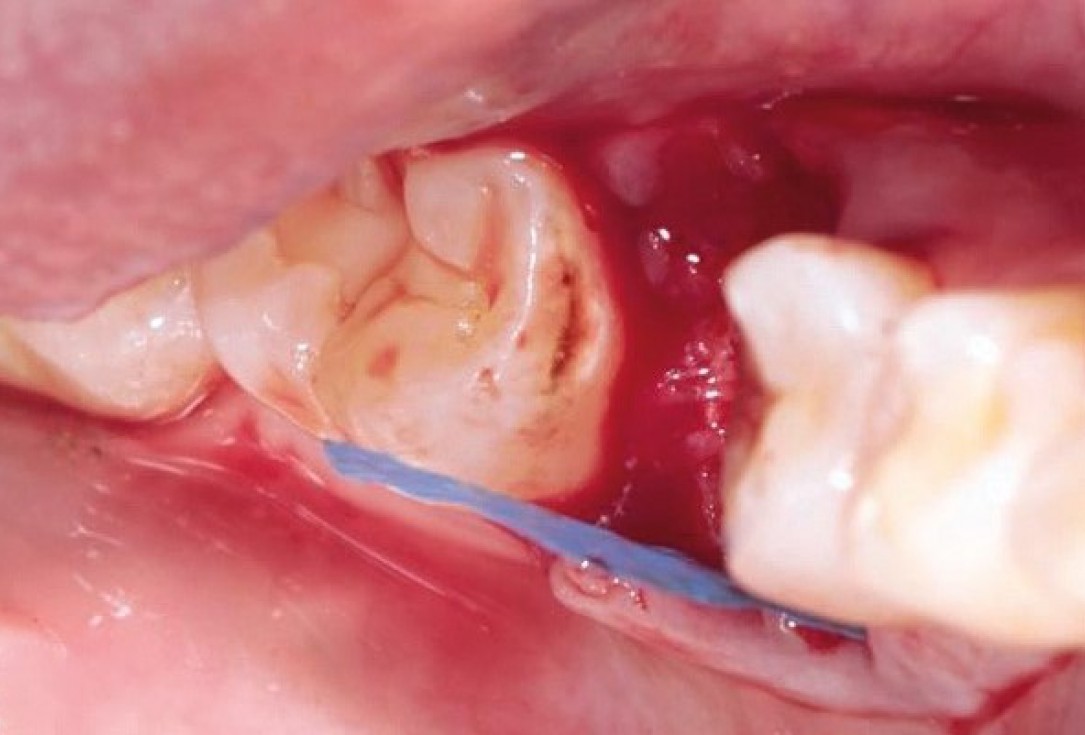

Situation after tooth extraction.